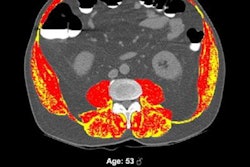

Axial images at L1 level, without (left) and with (right) segmentation overlay. Red indicates skeletal muscle, green indicates trabecular bone, yellow indicates visceral fat, and blue indicates subcutaneous fat. Segmented regions also include liver (beige) and spleen (orange), which were not evaluated as part of present analysis. (A) 78-year-old woman who underwent abdominopelvic CT at an outside institution. Bone tool returned L1 vertebral body bone attenuation of -146 Hounsfield units (HU), outside of reference range. Thus, the tool was deemed technical failure for bone tool. Failure was attributed to volume averaging of vacuum phenomenon within slice. (B) 64-year-old woman who underwent abdominopelvic CT at an outside institution. Bone tool returned vertebral body bone attenuation of -10,000 HU (default value for segmentation failure detected by tool), outside of reference range. Thus, the tool was deemed technical failure for bone tool. Failure was attributed to the presence of spinal fusion hardware. Images and caption courtesy of the American Journal of Roentgenology.The group reported that the three automated AI tools for measuring body composition were technically adequate in 97.7% of the CT exams. The failure rate was 2.3%, and these failures were primarily (88%) due to an image processing error caused by incorrect DICOM header voxel dimension information (i.e., an anisometry error).